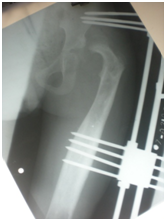

Figure 2 Across hip Naseer Awais External Fixator applied for control distraction of proximally migrated femoral head, 2mm per day.

Figure 3&4 Showing distraction started process is going on 2mm per day, to avoid Neuro-vascular injury.

Figure 5 showing Radiograph 3 weeks after distraction is on progress by applying NA Ex Fix.